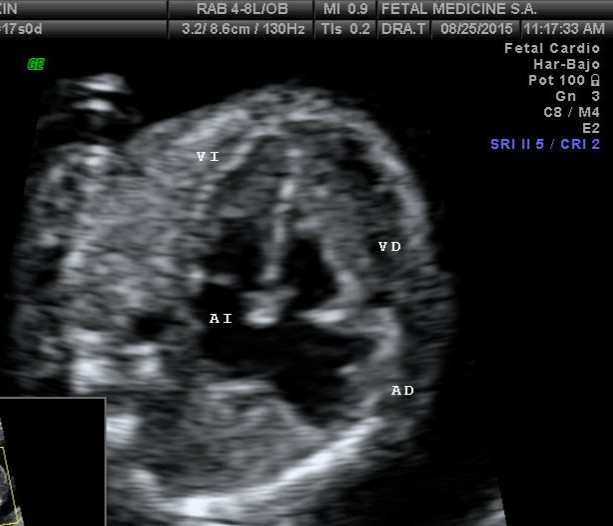

El diagnóstico precoz de la patología cardíaca fetal es uno de los aspectos en los cuales más se ha avanzado en los últimos años. Aunque todavia las tasas de detección son relativamente bajas, sobretodo en las anomalías de tracto de salida.

Sin embargo, en algunas el corte de cuatro cámaras cardíaco se puede alterar desde temprano.